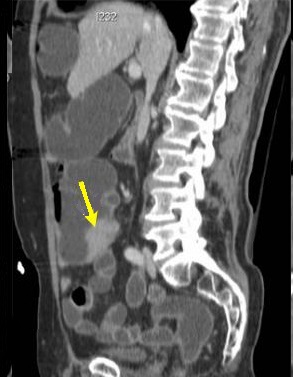

Aspect bourgeonnant

hyper-dense d'une adenocarcinoma du ceacum ( fleche

jaune ) . Image radiologique TDM en coupe coronale (

frontale ) . |

|

Même cas en coupe sagitale .

Aspect de masse du tumeur est bourgeonnant

hyper-dense intraluminale a bord irregulier (

fleche jaune ) |